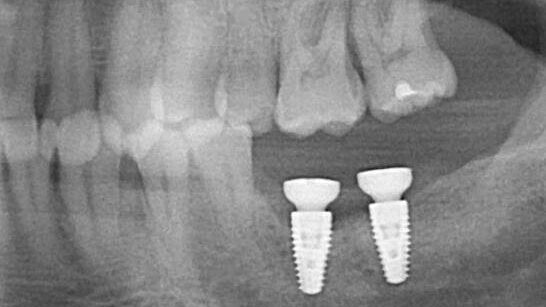

The patient presented on referral for retrieval of a fractured abutment from a 4.8 Straumann BL RC implant in the #18 site.